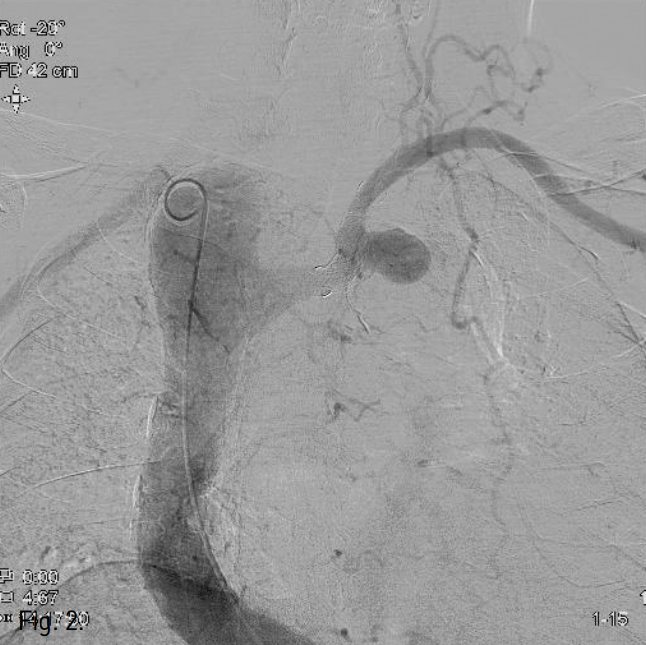

우측 대퇴동맥을 천자하여 8F vascular sheath를 삽입한 후 5F pigtail catheter를 이용한 대동맥조영술에서 하행대동맥에서 기시하는 aberrant left subclavian artery의 분지부 근처에 이전에 삽입한 stent-graft의 중간 부위에서 외측으로 aneurysm sac이 조영됨(Fig. 2A). 0.035-inch 유도철사가 stent-graft를 통과하여 aneurysmal sac내 들어가는 것으로서 stent-graft의 tear 및 type Ⅲ endoleak임을 확인함(Fig. 2B). Stent-graft의 metal component의 fracture는 없었음.

Fig. 2

A. Thoracic aortography shows an aneurysmal sac arising at the mid-portion of the aberrant left subclavian artery stent-graft.

B. A 0.035-inch guidewire was advanced into the aneurysm sac, through the stent graft, suggesting type III endoleak.